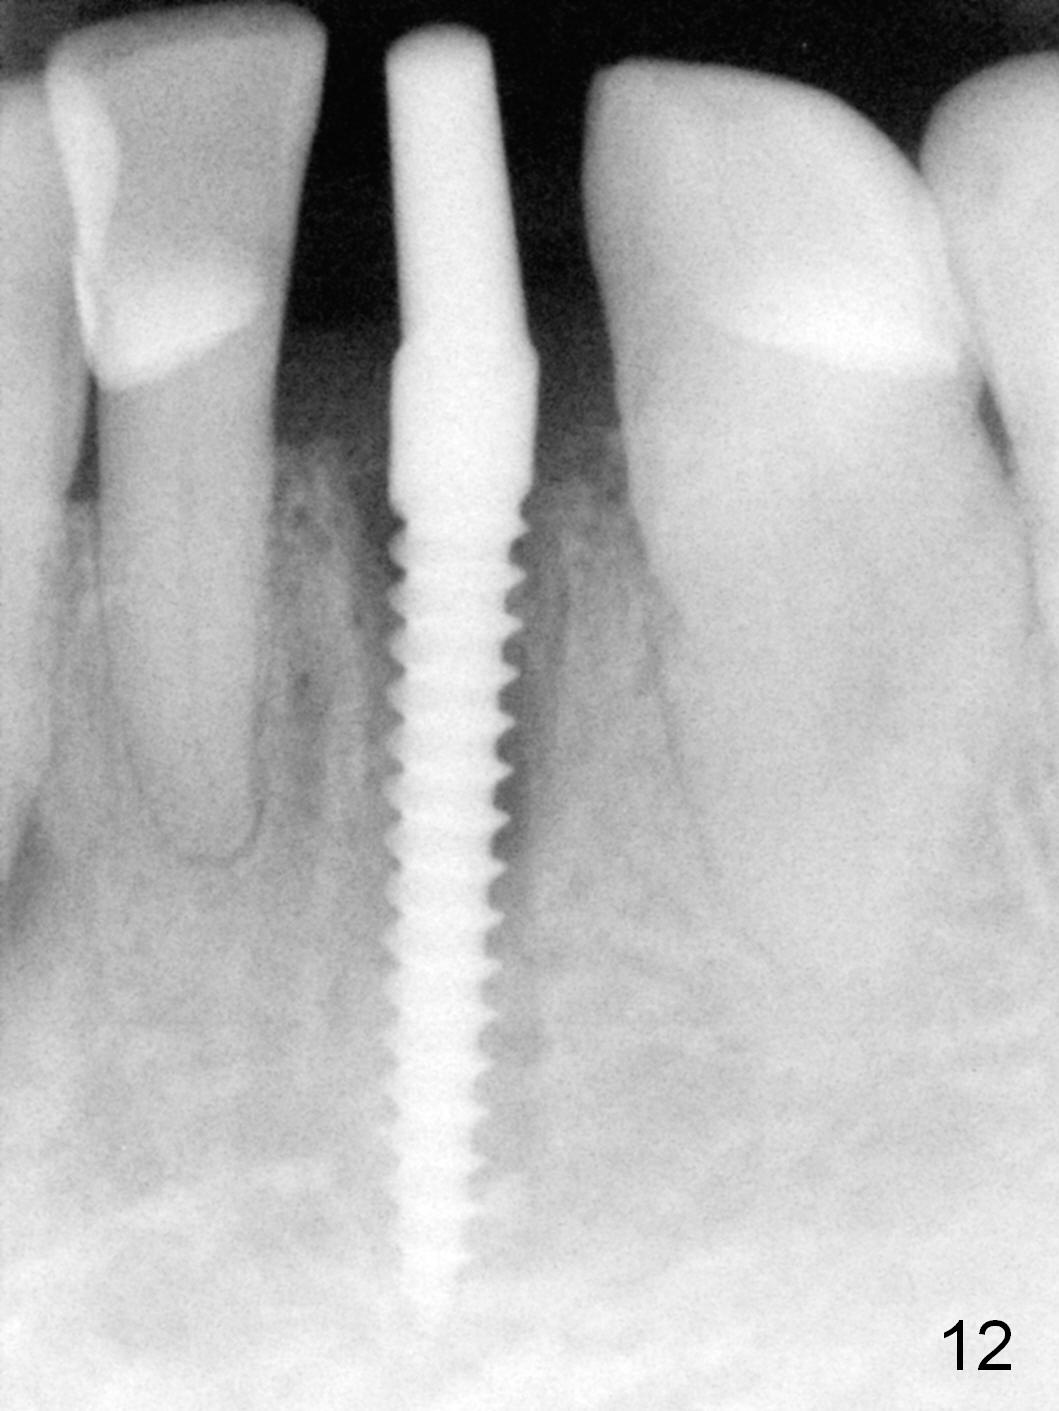

A 74-year-old man has several missing teeth (Fig.1).  His 1st goal is to replace the lower left lateral incisor (Fig.2).  The residual root has an apical lesion (Fig.3 *).  To describe intraop findings, a CT image of a different patient is used (Fig.4 coronal section; B: buccal; L: lingual).  After extraction, the buccal plate is found to be thin and low (Fig.5 arrowheads).  A 1.5 mm pilot drill (Fig.6 red line) is used to initiate osteotomy in the lingual plate of the socket.  Once the drill penetrates the lingual plate, the trajectory changes and the depth is 17 mm from the gingival margin (Fig.7).  A PA is taken (Fig.8); it appears that the osteotomy can be extended more apically.  When the pilot drill extends to 20 mm, there is sudden empty feeling.  The lingual plate has perforated (Fig.9).  A new osteotomy is established buccally (Fig.10 pink).  To avoid buccal plate perforation, especially in the buccal undercut area (>), the coronal end of the drill has to be tilted buccally (<--).  An angled abutment (3x20 mm, 15°) is placed (Fig.11,12).  The abutment is modified (Fig.13,14) to accommodate an immediate provisional (Fig.15,16 P).  Perio dressing is to be applied to prevent the bone graft from getting dislodged buccally (Fig.15).  The dressing is in place 7 days postop (Fig.17).